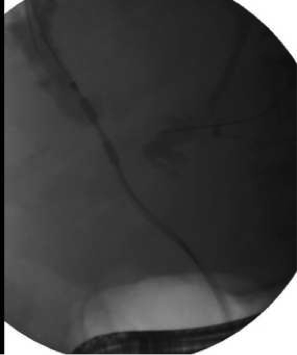

Endoscopic Retrograde Cholangiopancreatography (ERCP)

Endoscopic Retrograde Cholangiopancreatography (ERCP) is a procedure that allows for alleviation of obstruction of the ducts that drain the liver/gallbladder and pancreas.

During ERCP, access is obtained into either the bile duct or the pancreatic

duct and the opening is enlarged using a technique called a sphincterotomy.

A balloon is used to inflate high-up in the duct to sweep out stones causing

an obstruction. In some cases where a stricture is present (a narrowing

of the duct either from inflammation or cancer), a stent is placed which

stretches the narrowed area open over time and allows for continued drainage

even after the procedure concludes. Biopsies of the bile duct or pancreatic

duct may also be obtained when necessary.